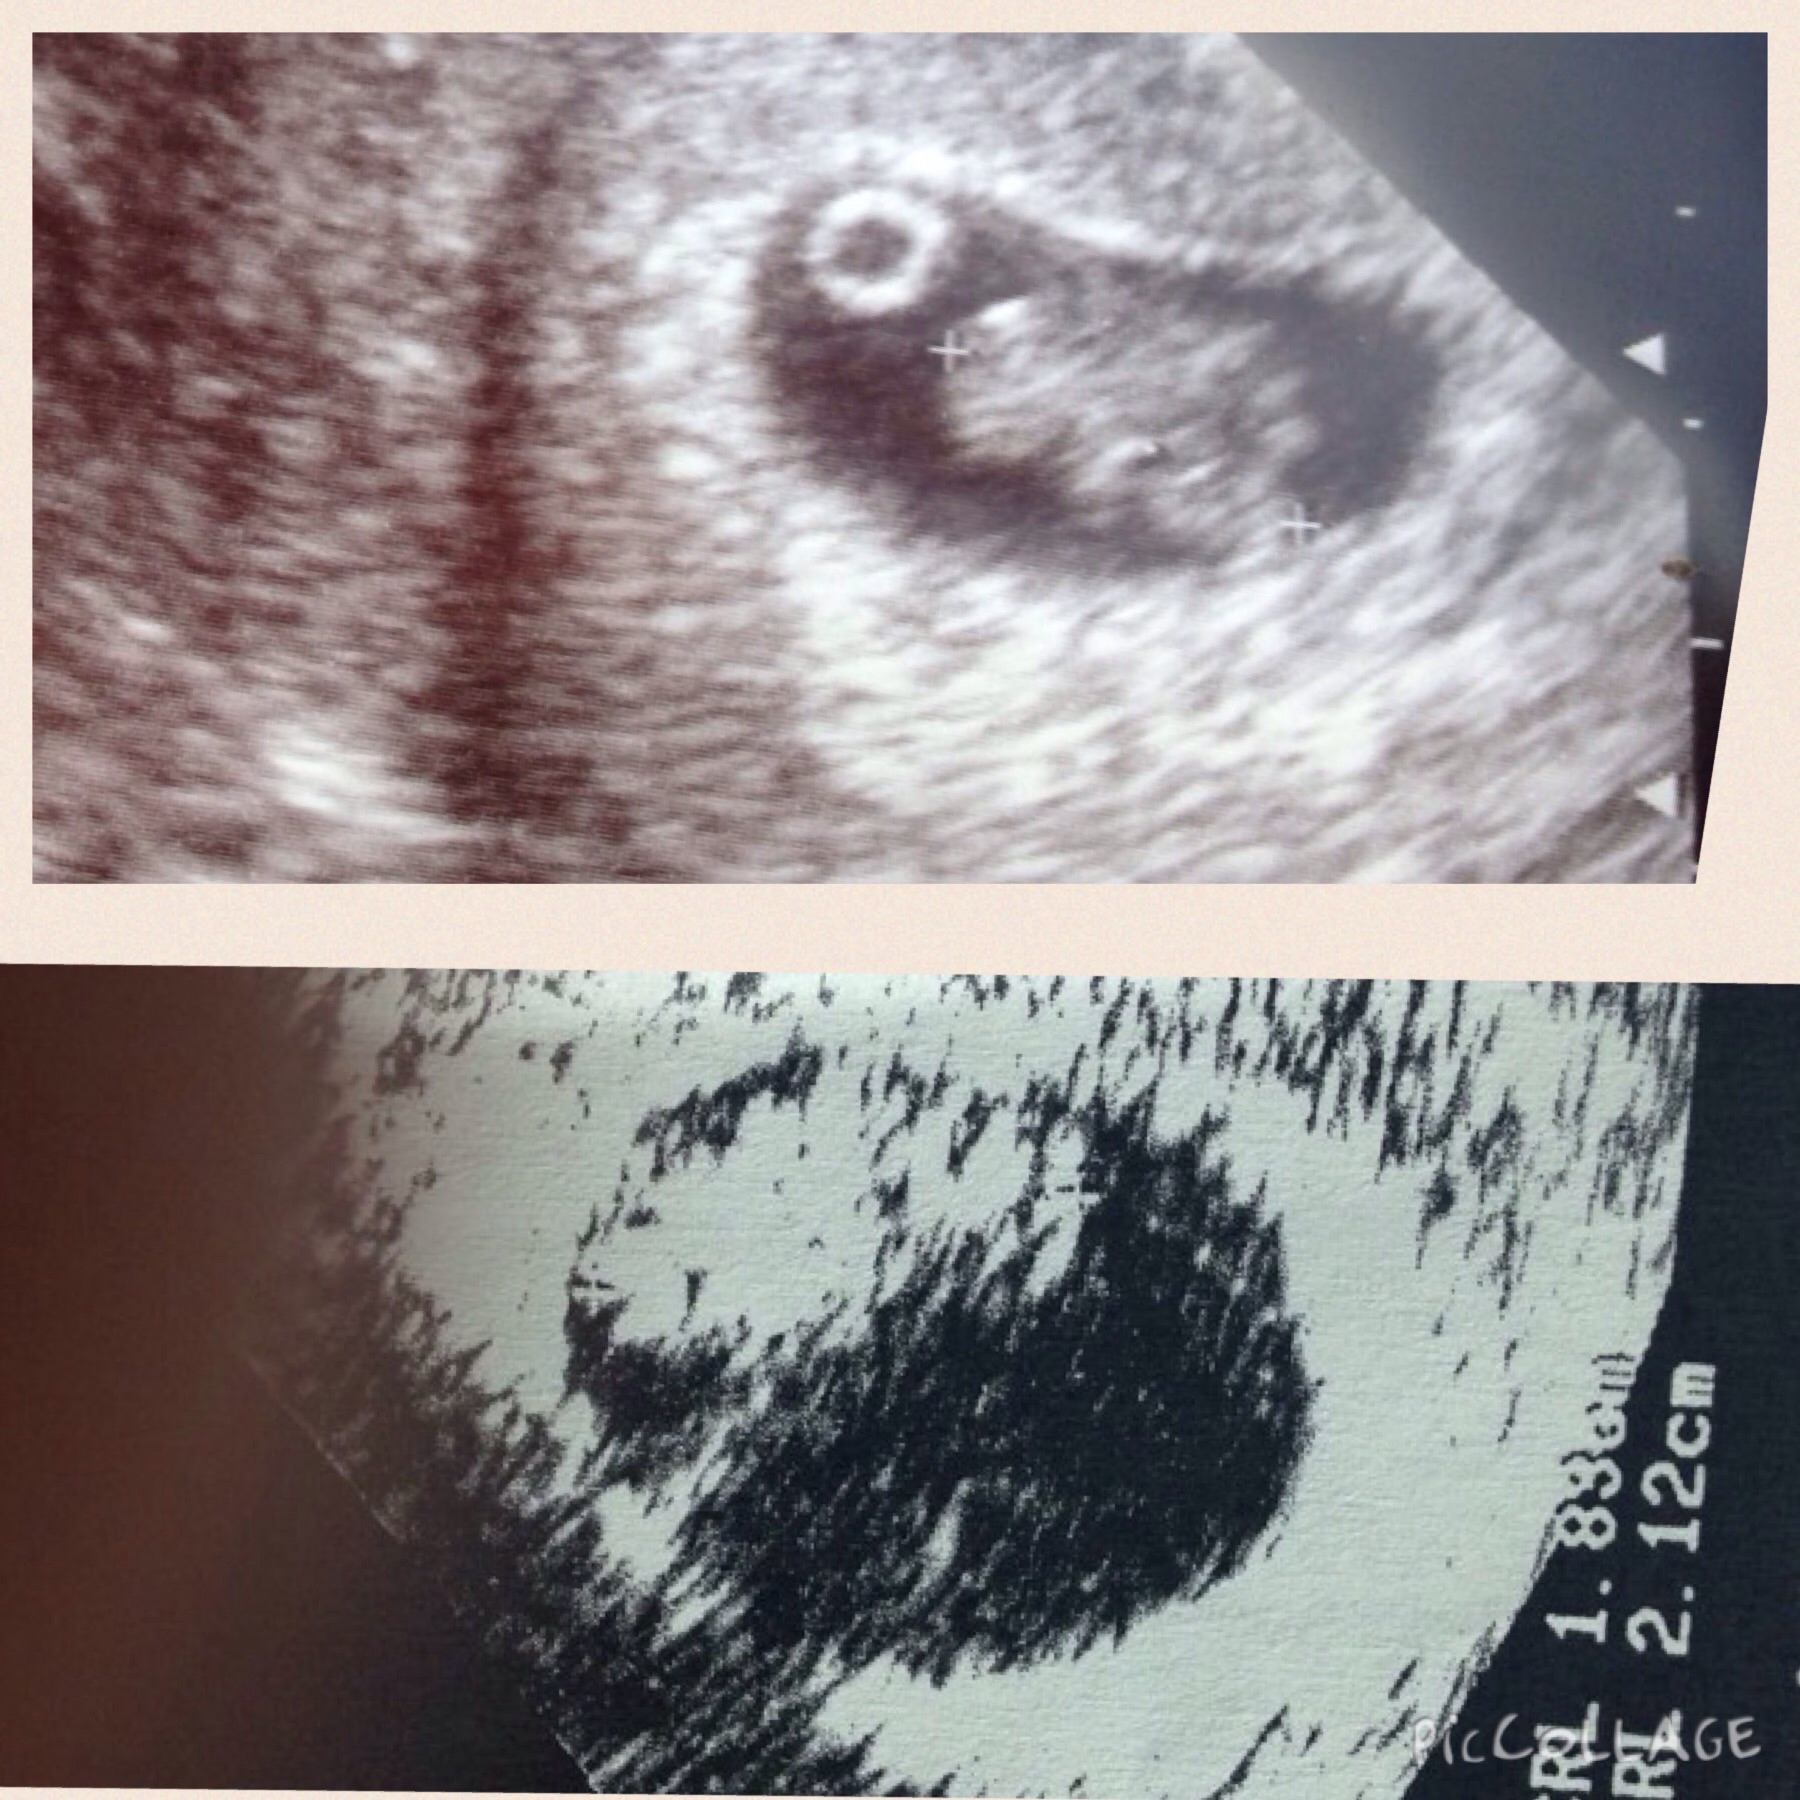

I had my ultrasound done on Tuesday and baby looked good with a heart rate of 173, but measured small. According to my lmp, I should have been 9wks 2dys. The baby measured at 7wks 3dys. I know I ovulated late because of opks and so I think I should have been 8wks 5 dys...

I went in for my ultrasound this morning and it was not good news. The baby had only grown 2 days and there was not a heartbeat anymore. I will be having a D&C tomorrow.

I had my ultrasound done this morning. The baby only measured 7wks 5dys and no longer had a heartbeat. I am going to have a d&c tomorrow (since I took progesterone, the doc said it could be weeks if I wait to try to miscarry on my own).